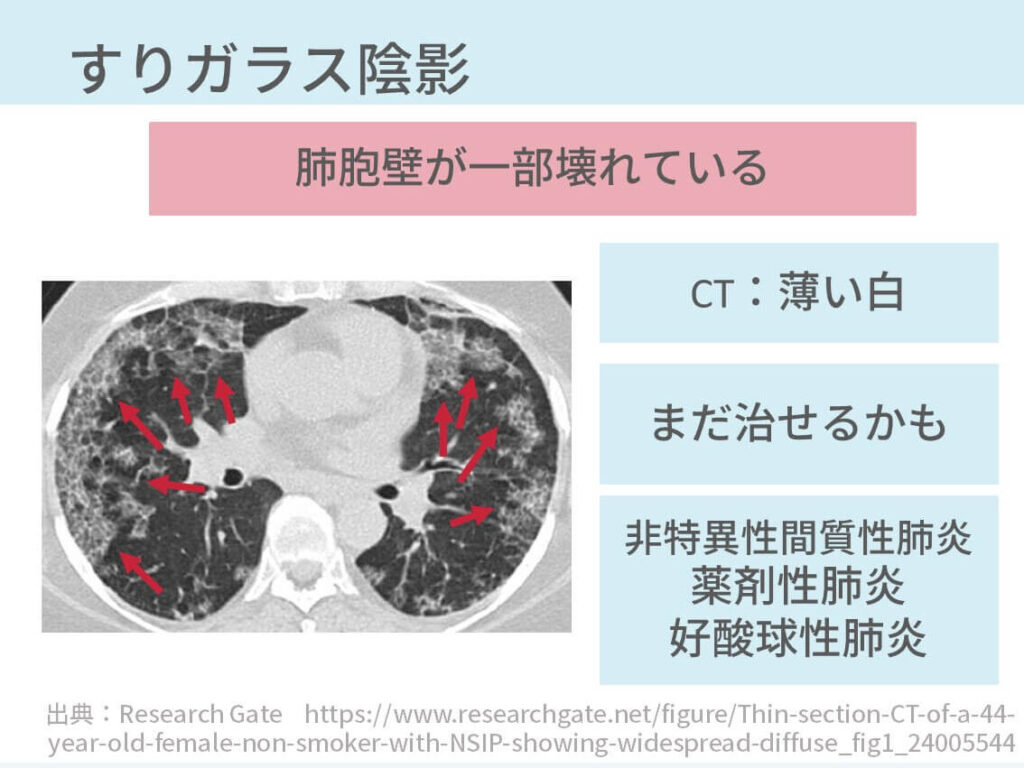

NMC Diagnosis。0b3b59392e9eaf6a38d2ac37cd75fc。間質性肺炎 | 印西そよかぜ内科・呼吸器内科。画像診断 Vol.41 No13. 特集『なぜによくわからない間質性肺炎。「肺炎の画像診断と最新の診療」藤田次郎定価: ¥ 12,540#藤田次郎 #本 #BOOK #健康 #医学